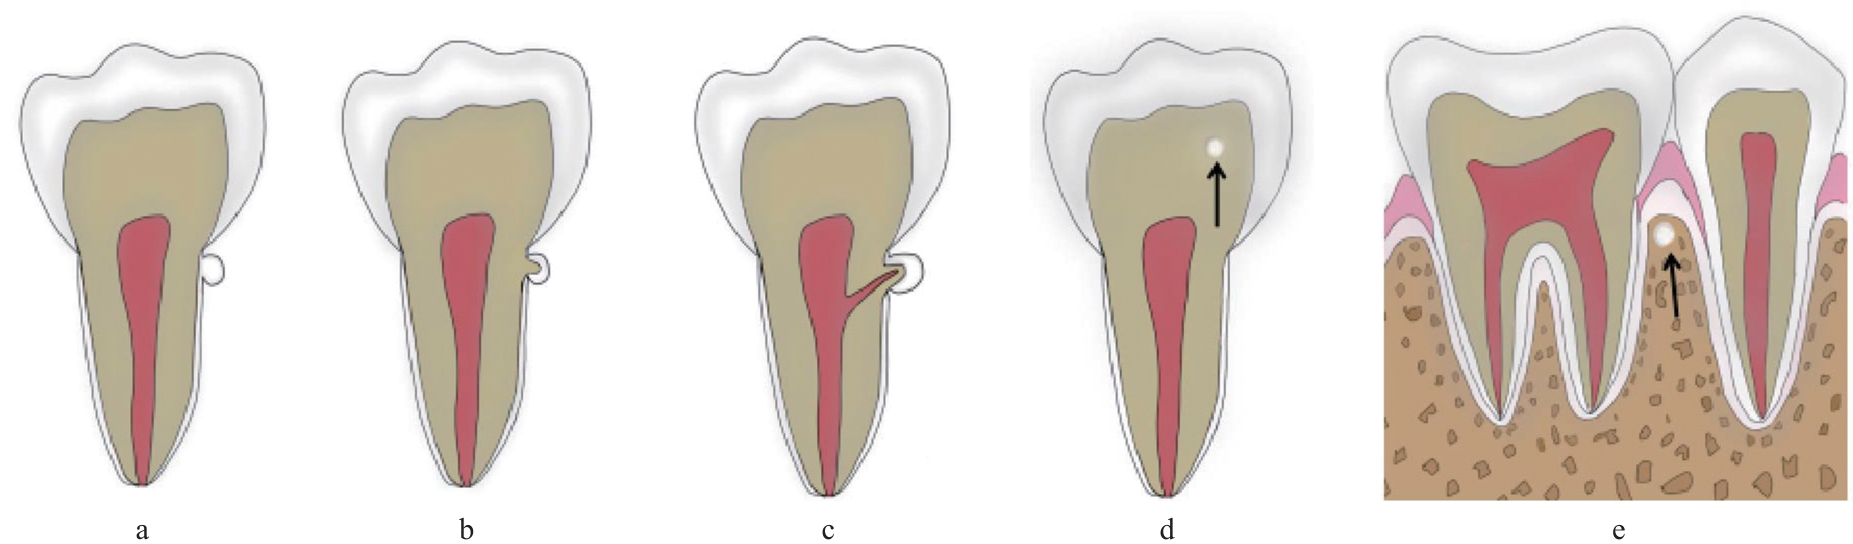

Fig 2

Classification diagrams of enamel pearls"